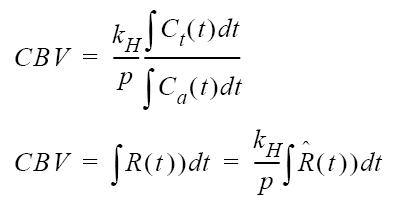

| CBV |  |  |

| table legend | p = density of brain tissue R(t) = Residue function kH = correction factor | |

Relative Blood Volume

Relative Blood Volume (rCBV) describes the blood volume of the cerebral capillaries and venules (not arteries) per cerebral tissue volume.